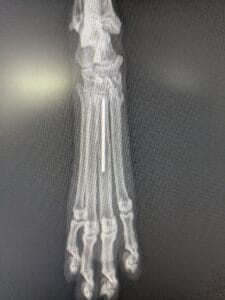

犬の中手骨・中足骨骨折について|症例をもとに治療法と注意点を解説中手骨/中足骨骨折

骨折しやすい手の甲・足の甲部分である中手骨・中足骨に起こる骨折。今回はその分類「中手骨/中足骨骨折」の症例をもとに、治療の流れと術後のケアをわかりやすく解説します。